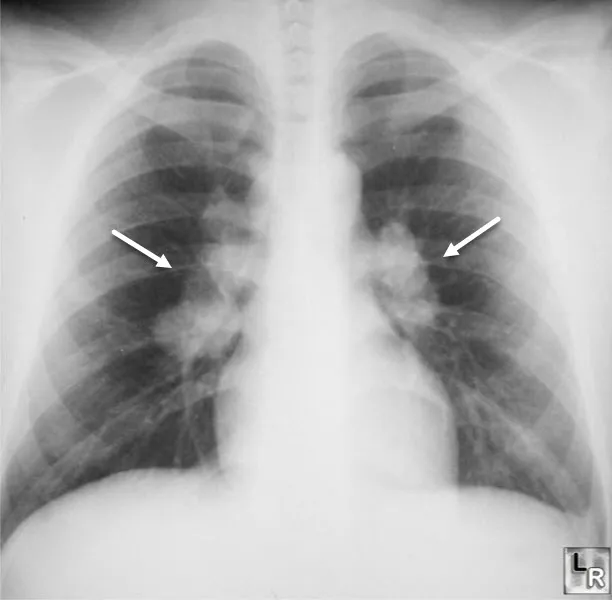

| Sarcoidosis | Perilymphatic nodules, upper lobe | Variable, 60-80% | Lymphocytosis >15%, CD4/CD8 >3.5 | Well-formed non-caseating granulomas | Steroids 70-80% response |

💡 Master This: CD4/CD8 ratio >3.5 on BAL has 94% specificity for sarcoidosis (normal 1.5-2.0). Combine with compatible imaging and clinical context to avoid biopsy in 60% of cases. However, biopsy remains gold standard to exclude malignancy and infection.